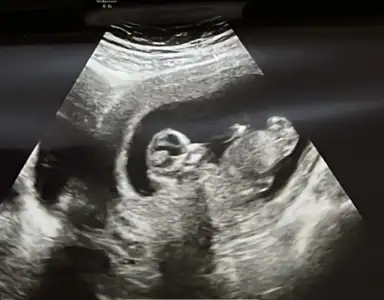

Nub ramzi tahmin edeyim kızlar

Buna göre bakarsam kız derim kuzum :)

Saol kuzum☺️ Doktorumda böyle bacak arasını görünce kız gibi ama %70 dedi kesin konusmak istemedi. Bide internetten baktım kız bebekte olan çıkıntı var ultrason fotoğrafımızda. Ama hayırlısı tabi ilk bebeğimiz kız erkek farketmez sağlıklı olsunda🥰

Benim bebek yan durduu hep Dr izledi ve nuba göre kız olduğunu söyledi gerçekten de Bİ nub gözüküyor, net de konuşamam dedi 12ye gidiyordum benn de o sıra.. Bakalım noluyo :) 1 ay snra söylicek :)